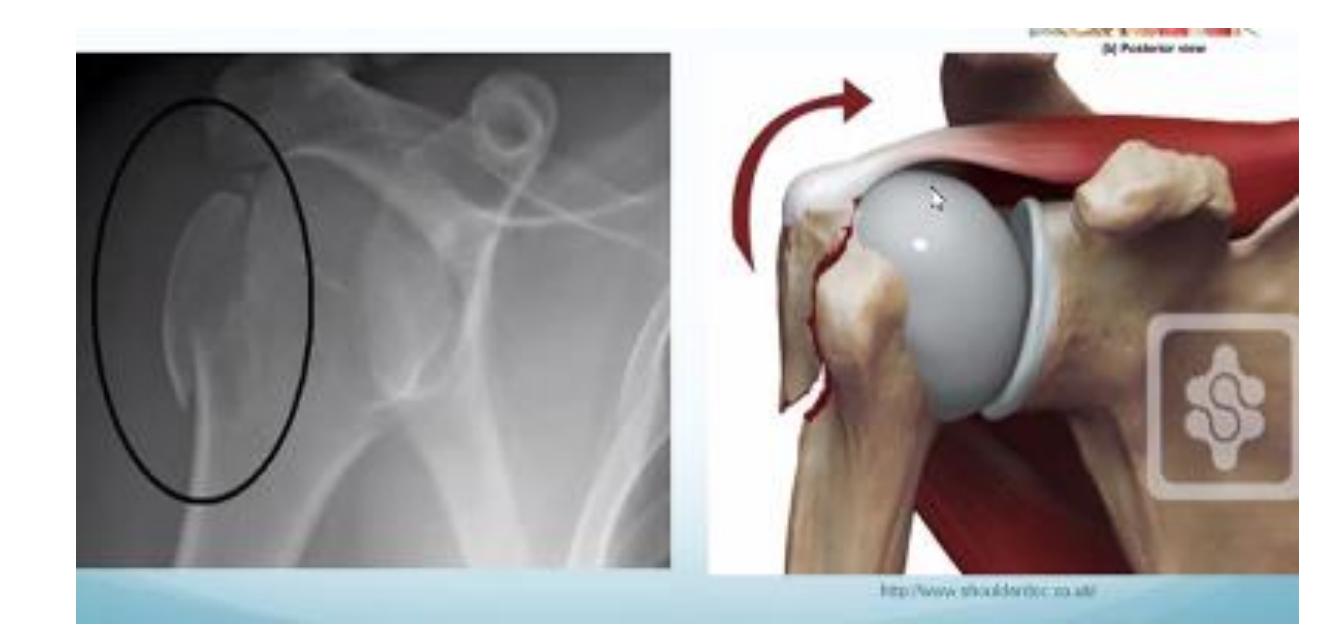

Hill-Sachs Lesion

What does this photo show?

- Hill-Sachs lesion

18-year-old male presented after sport injury and unable to do internal rotation of right shoulder. What is the name of the injury seen in the figure?

- Hill-Sachโs defect

18-year-old male presented after sport injury and unable to internally rotate his left shoulder. What is the diagnosis?

A case scenario about a male with anterior shoulder dislocation. What does the figure 1b show?

reverse - Hill sachs lesion

What do you see in this image?

- Hill sachs lesion